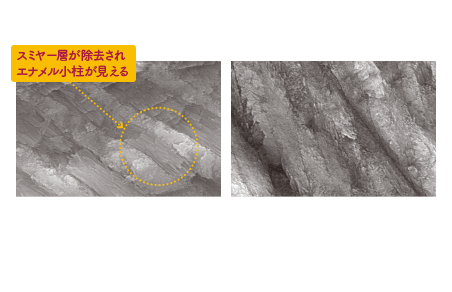

塗布後待ち時間「0秒」でも、高い接着力

臨床実績があるリン酸エステル系モノマー「MDP(10- methacryloyloxydecyl

dihydrogen phosphate)」とカルボン酸系モノマー(4-MET)を配合することに

より、エナメル質、象牙質と共に強固に接着。溶媒に揮発性の高いアセトンを使用

することにより、ボンディング層から水を効果的に除去。また、親水性の高い

HEMAを配合していないため吸水しにくく、長期的な接着耐久性が期待できます。